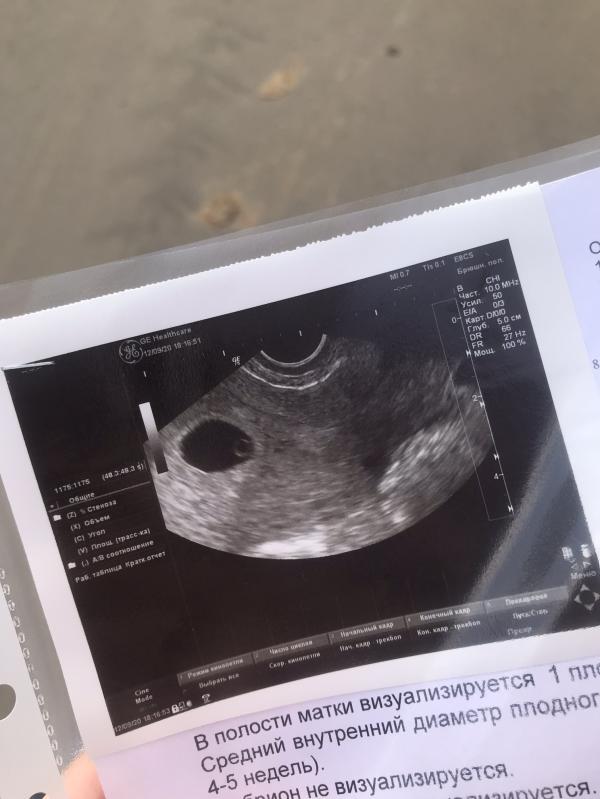

Привет, наша маленькая большая любовь 🤍

6 недель 2 дня.

Поздравляю 🥳 только странно почему пишут эмбрион не визуализируется , если эта белая точка это и есть малыш ) ну у меня так было на первом узи, мне так гинеколог сказал)

Спасибо 😊 Она сказала, что это желточный мешочек вроде)